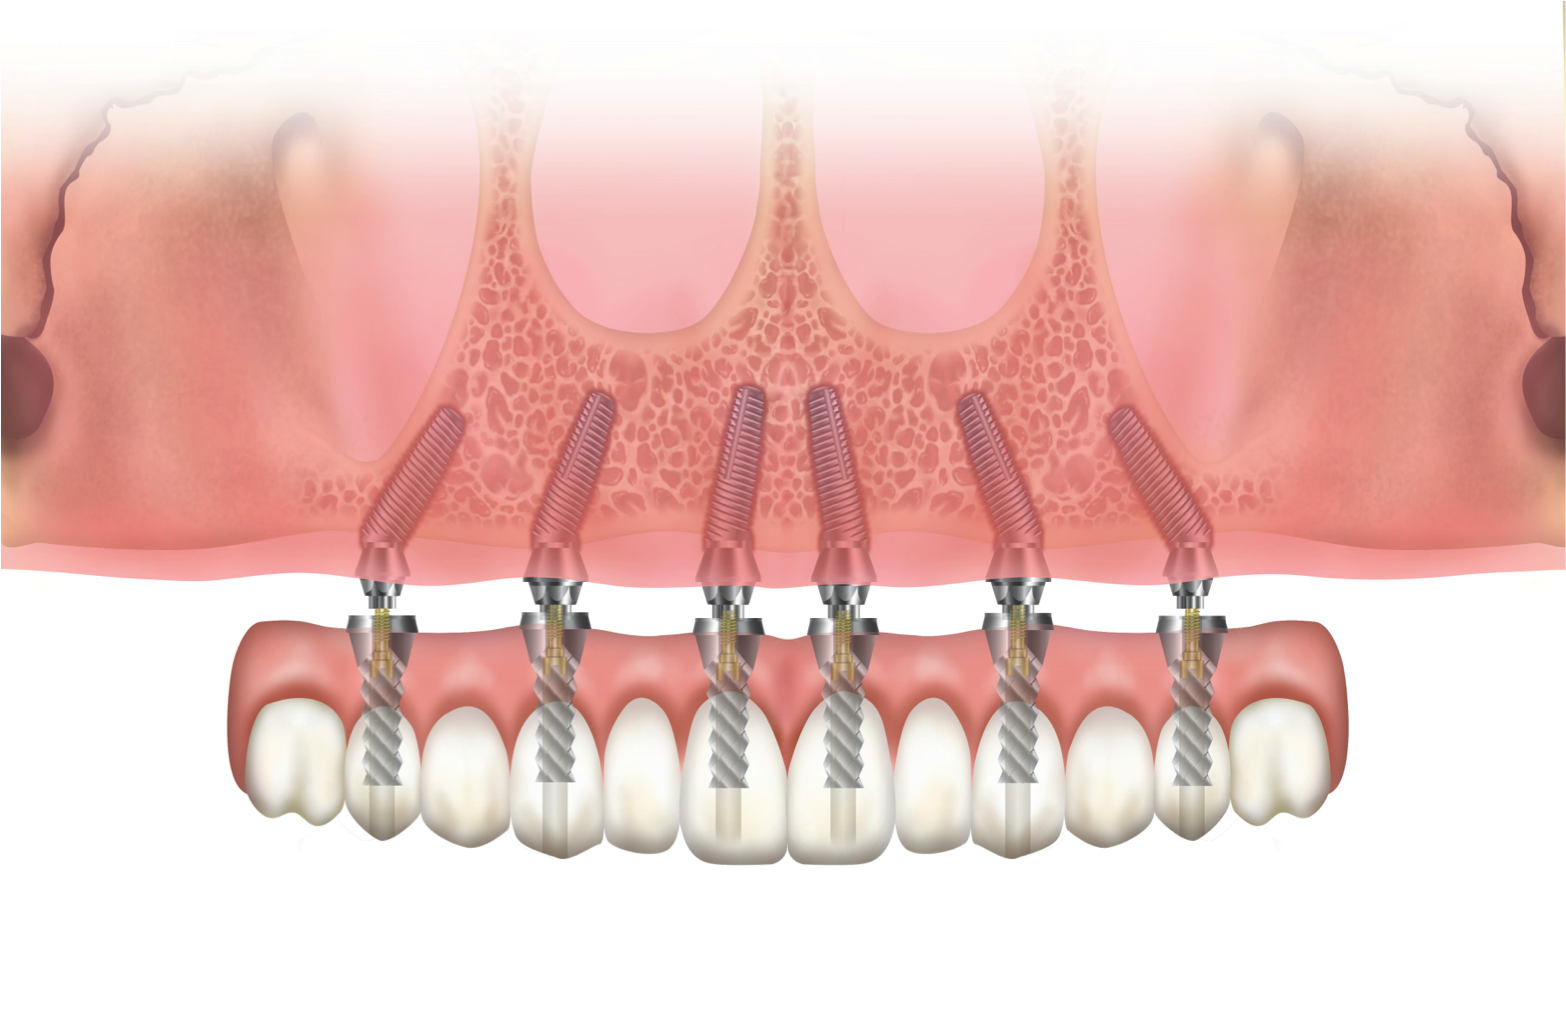

The author has used the dual-axial implant fixture unconventionally in the anterior mandible in an orientation that avoids perforation into the floor of the mouth (Figure 8).5 Dual-axial implants have also been used to avoid critical anatomic structures, such as the maxillary sinuses (Figure 9) and inferior alveolar nerves (Figure 10),47 thereby reducing the need for grafting procedures. Because these implants have subcrestal angular correction, they can be used with standard uniaxial abutments in a common path of insertion, thus enabling screw retention.

With the increased application of this concept, more options have been introduced, including 24-degree and 36-degree correction (Figure 11 through Figure 13). At present, larger angular corrections are available with external hexagon connection systems, while the 12-degree connection is also available in most internal connection configurations.

Fig 8. Reverse rotation application in the anterior mandible to avoid apical perforation (arrow) of the floor of the mouth.

Figure 8